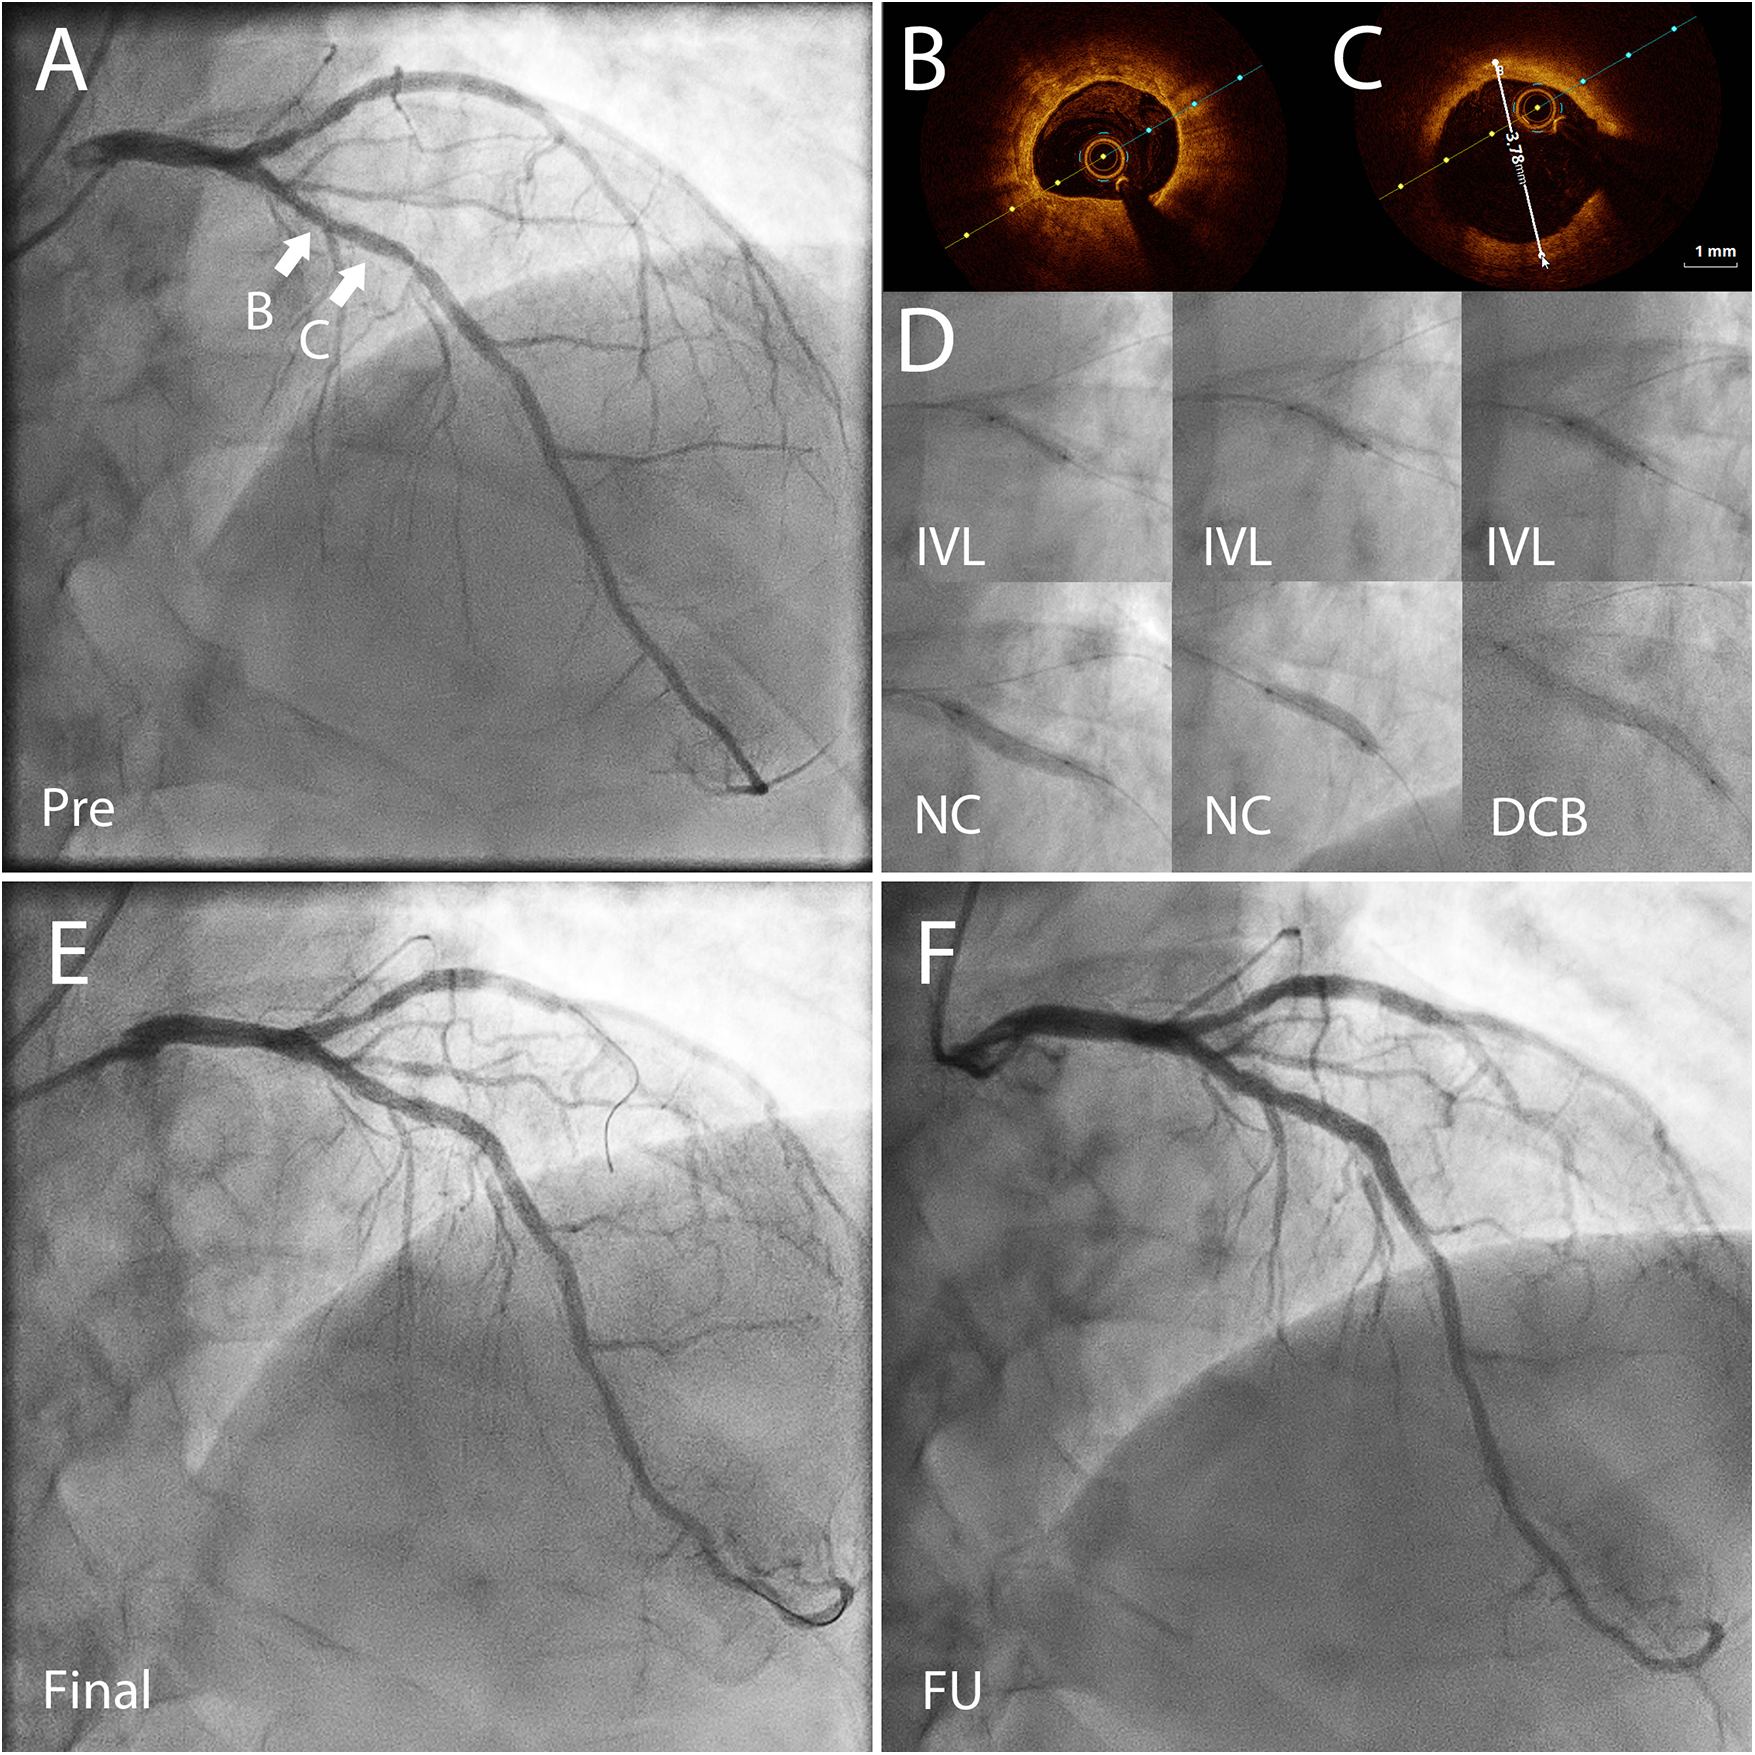

Figure 3

Coronary angiography (CAG) and optical coherence tomography (OCT) images of a 72 yr old patient presenting with CCS3 chest pain. The risk factors for coronary artery disease included high blood pressure and hypercholesterolemia. He had a high bleeding risk due to a permanent anticoagulation with warfarin treatment (APC resistance). (A) CAG before percutaneous coronary intervention (PCI) shows severe coronary stenosis in the left anterior descending (LAD) artery. FFR was 0.72 in the distal LAD demonstrating significant reversible myocardial ischemia. (B) OCT before PCI showed concentric calcification. (C) OCT before PCI showed the vessel reference diameter of 3.78 mm distally from the lesion B. (D) First, non-compliant (NC) and OPN NC balloons were used but they bursted. Thereafter, the severely calcified lesion was predilated using with 3.5 × 12 mm Shockwave™ balloon for 80 pulses, and then further predilation was performed with a 3.5 mm NC-balloon. After predilation there was no significant recoil (>30%) or flow-limiting dissection, and the lesion was treated with two paclitaxel drug-coated balloons (DCB) 3.5 × 40 mm and 3.5 × 15 mm for 60 s. (E) The final result after IVL + DCB treatment. (F) CAG almost two years after the index procedure done before planned aortic valve replacement surgery demonstrating a good long-term result of the treated area. CCS, Canadian cardiovascular society angina grade; PCI, percutaneous coronary intervention; FFR, fractional flow reserve; OCT, optical coherence tomography; OPN NC, super high pressure non-compliant balloon catheter; IVL, intravascular lithotripsy.